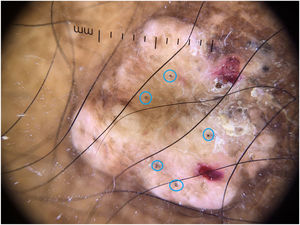

There is no description in the literature of the dermoscopy of lobomycosis lesions. The findings of this case show the dermoscopy performed on a nodular lesion on the leg of this patient, with areas of hyperpigmentation interspersed with hypopigmentation, scales, blood crusts, and several black dots. Vascular structures were not observed (Fig. 4).